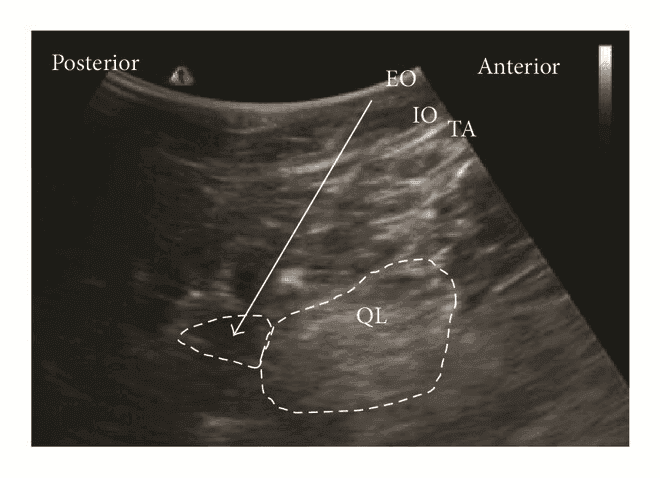

Задня QL-блокада (тип 2 QLВ, QLB2)

Для QLВ2 конвексний/лінійний датчик розташовують в поперечній площині по середньоаксилярній лінії та зміщують назад, як і при QLB1, доки не стане видимим задній край квадратного м'яза попереку. Голку вводять in-plane з латеральної сторони датчика до моменту, коли її кінчик опиниться біля заднього краю m. quadratus lumborum. Місцевий анестетик вводять в середній шар тораколюмбальної фасції поблизу поперекового міжфасціального трикутника (LIFT). Правильне розміщення кінчика голки має призвести до поширення місцевого анестетика вздовж середнього шару fascia thoracolumbalis до паравертебрального простору.